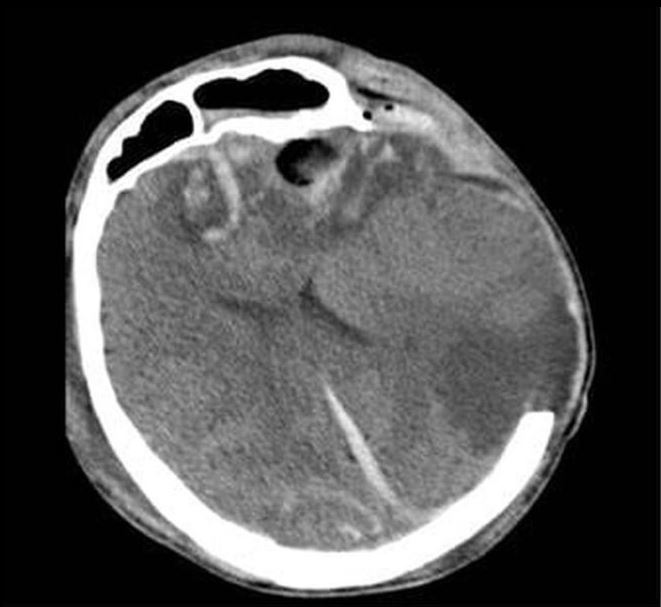

Phim CT não của 2 bệnh nhân

Tại Bệnh viện Nhân dân 115, bệnh nhân G.A nhập viện trong tình trạng hôn mê sâu, phải thở máy nội khí quản. Kết quả chụp CT sọ não cho thấy dập não xuất huyết rải rác nhiều vị trí, phù não lan tỏa nặng, tiên lượng rất dè dặt, nguy cơ tử vong cao. Bệnh nhân được điều trị tích cực tại Đơn vị Hồi sức ngoại khoa, Khoa Gây mê Hồi sức với sự theo dõi sát sao của ê-kíp chuyên môn.

Người mẹ, bà G.N. cũng trong tình trạng rối loạn tri giác, dập não thái dương lượng lớn. Sau hội chẩn kỹ lưỡng, các bác sĩ quyết định lựa chọn phương pháp điều trị bảo tồn nhằm hạn chế tối đa tổn thương thứ phát. Hướng điều trị này cho thấy hiệu quả rõ rệt khi người bệnh dần tỉnh táo, cải thiện khả năng giao tiếp và chức năng ngôn ngữ. Sau 10 ngày điều trị tại Khoa Ngoại thần kinh, bà G.N. hồi phục tốt và được xuất viện.